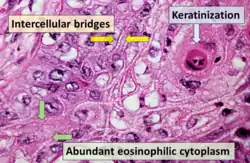

Squamous cell carcinoma with typical histopathology features.

Squamous cell carcinoma with typical histopathology features. -